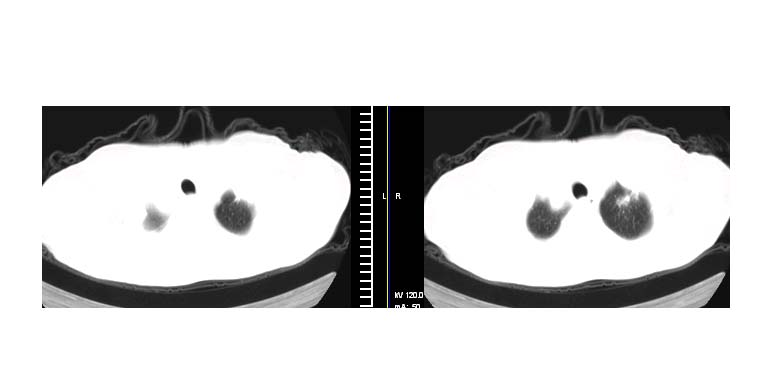

标题: CT11087:男性,82.咳嗽一周.抗炎治疗4-5天效果不明 [打印本页]

标题: CT11087:男性,82.咳嗽一周.抗炎治疗4-5天效果不明

考虑左上肺癌,似与左侧肋骨关系密切?

左上肺周围型肺癌伴纵隔淋巴结转移

左上肺实质性肿块,浅分叶 毛糙 胸膜凹陷征 纵隔淋巴结肿大——支持:左肺上叶周围型肺癌!

左上肺软组织肿块,有分叶,短毛刺,气管旁间隙见有肿大淋巴结,考虑左上周围型肺癌伴纵隔淋巴结转移。